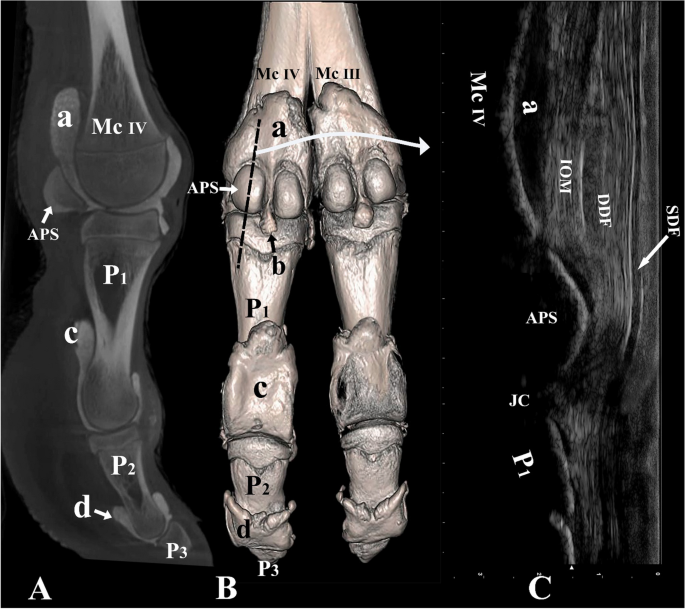

Palmar and lateral view of the left distal forelimb and digit IV. (A) Sagittal plane CT image; (B) three-dimensional reconstruction (the black dotted line indicating the placement of the ultrasound probe over the abaxial proximal sesamoid bone), and (C) longitudinal palmar ultrasound image of the metacarpophalangeal joint. Mc III distal end of metacarpal bone III, Mc IV distal end of metacarpal bone IV, P1 proximal phalanx, P2 middle phalanx, P3 distal phalanx, APS abaxial proximal sesamoid bone, a proximal palmar pouch of the metacarpophalangeal joint, b distal palmar pouch of the metacarpophalangeal joint, c proximal palmar pouch of the proximal interphalangeal joint, d proximal palmar pouch of the distal interphalangeal joint, IOM interosseous medius muscle, SDF superficial digital flexor tendon, DDF deep digital flexor tendon, JC joint cavity.

Palmar/plantar, the IOM, SDF, and deep digital flexor (DDF) muscles bifurcate in the distal region of the metacarpal/metatarsal bone. The lateral and medial tendinous band of the IOM inserts on the proximal sesamoid bones of digits III and IV (Figs. 3C,D, 4C, 7C). It does not extend a dorsal supporting branch to fuse with the extensor tendons. As the SDF and DDF move over the metacarpophalangeal/metatarsophalangeal joint, the SDF gives rise to the manica flexoria (Fig. 3D). The middle part of the tendon becomes thin and the borders of the tendon remain thick as it moves over the proximal sesamoid bones (Figs. 3D, 7C). Distal to the metacarpophalangeal/metatarsophalangeal joint, the SDF forms a slit and allows the tendon of the DDF to move through the manica flexoria (Figs. 2C, 3D). The thickness of the DDF tendon is uniform as it moves over the metacarpophalangeal/metatarsophalangeal joint and through the manica flexoria (Figs. 3D, 7C). The SDF inserts on the proximal flexor surface of P2, and the DDF inserts on the flexor surface of P3.

Palmar/plantar, the distal ends of the metacarpal/metatarsal bones, the IOM, SDF, DDF, the manica flexoria, the large metacarpophalangeal/metatarsophalangeal pouches, the axial and abaxial proximal sesamoid bones, the proximal end of P1, and the small pouch extending distally between the two proximal sesamoid bones were identified (Figs. 3C, 7C). The insertion of the IOM on the proximal sesamoid bones could be viewed under ultrasound guidance (Figs. 3C, 7C). The DDF and SDF were clearly seen on ultrasound imaging (Figs. 3C, 7C). Figure 7C indicates the thinning of the SDF as it moves over the proximal sesamoid bones and forms the manica flexoria. The proximal and distal interphalangeal joints and the distal ends of the P1, P2, and P3 could not be viewed via a palmar/plantar aspect because of the presence of the footpad.

Computed tomography

The CT scans in this study provided three-dimensional images with exceptional detail, allowing for a clear visualization of the distal limb including joint cavities, recesses, and pouches of the metacarpophalangeal/metatarsophalangeal joints, as well as the proximal and distal interphalangeal joints (Figs. 3A,B, 5A,B, 6A,B, 7A,B). The CT results were in accordance with the ultrasound findings, supporting the accuracy of our anatomical observations.